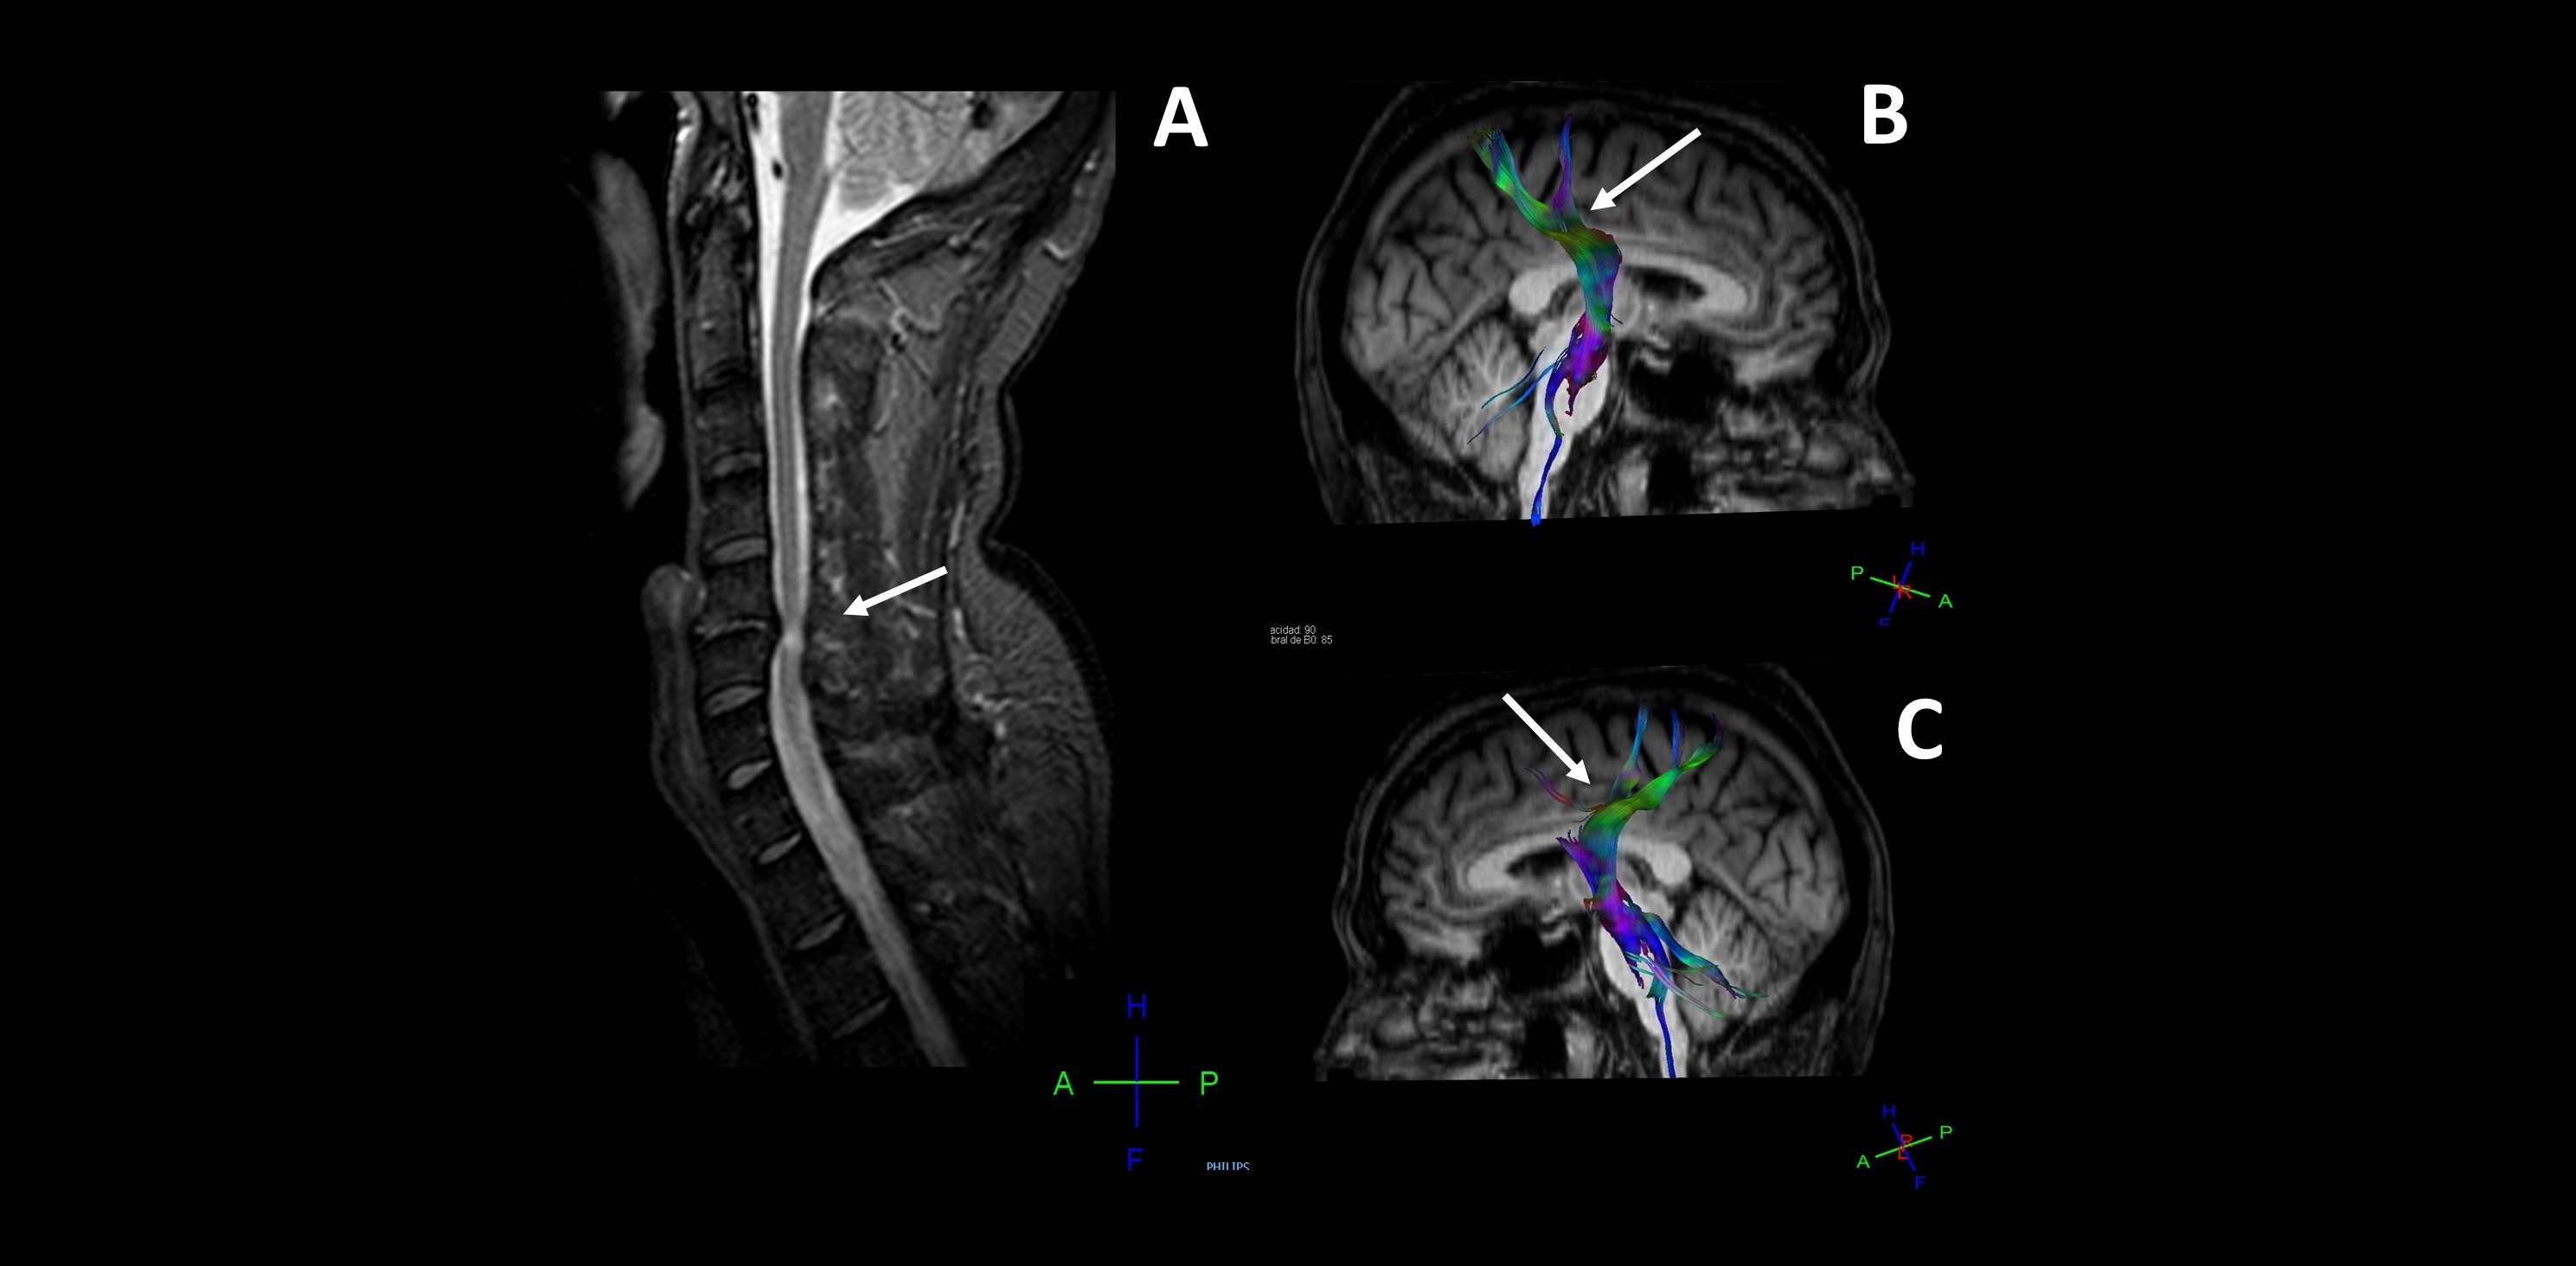

Detectan daño cerebral en pacientes con hernias cervicales mediante técnicas de neuroimagen e inteligencia artificial

16/01/2020